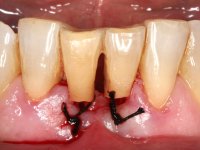

• Extraction of teeth 41 and 31 keeping the crowns of the same teeth as a provisional situation.

Splinting of teeth 41 and 31 to the adjacente teeth with a metallic mesh allowed us to temporarily resolve the esthetic situation and simultaneously avoid the use of a removable prosthesis, during the healing of the sockets and also during the osteo-integration phase of the dental implant.